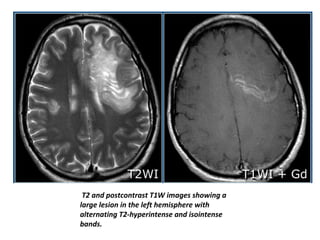

T2 and postcontrast T1W images showing a

large lesion in the left hemisphere with

alternating T2-hyperintense and isointense

bands.